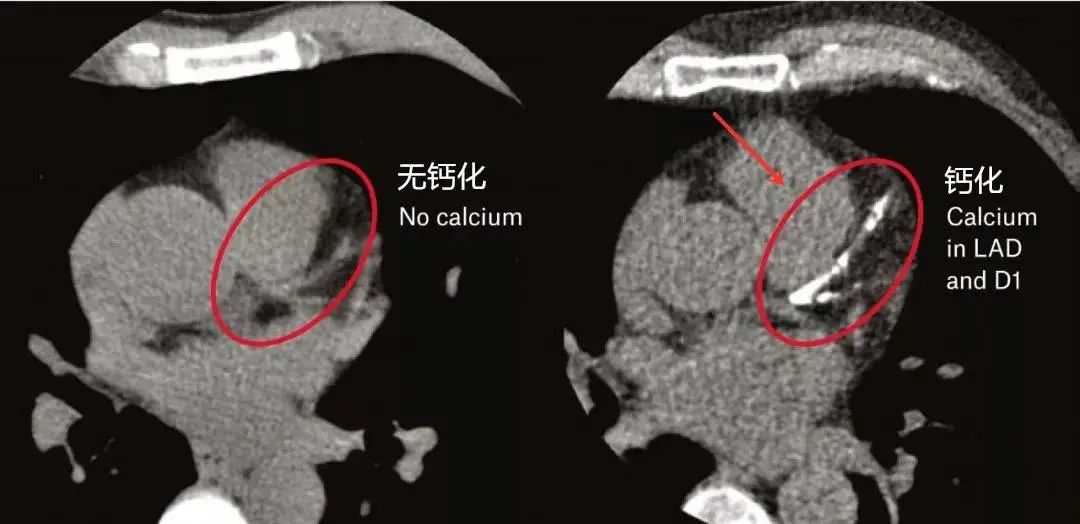

冠脉钙化积分(Coronary Artery Calcification Score, CACS)是使用CT对冠脉整体的钙化情况进行量化评估,通过普通的CT平扫来完成,无需注射碘造影剂。可有效评估出受检者5~10年冠心病事件发生风险,提早筛查,尽早干预。

冠状动脉钙化积分标准是通过CT检查,对不同的结果进行量化评估,一般分为五级。